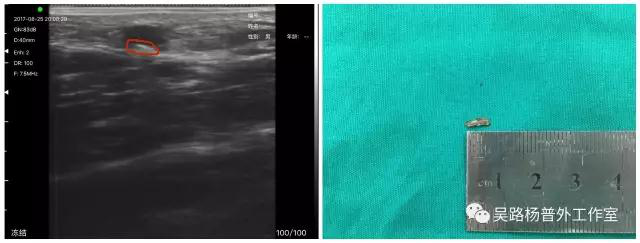

Preoperative and intraoperative localization of Abnormal objects in the body Abnormal objects injection intobodies,

because of the different angles and speed, the distance and depth of the wound is sometimes difficult toknow,

intraoperative C-arm perspective can only locate metalobjects, can not do non-metallic .

The wireless ultrasound can not only be positioned before operation, but also can be used in real-time operation.